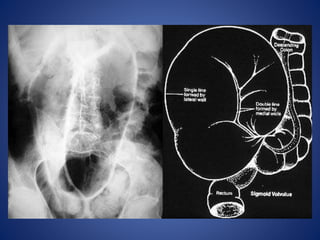

Volvulus x ray: Sigmoid volvulus -

'coffee bean' sign

The sigmoid colon is very dilated because it is twisted at the root of its

mesentery in the left iliac fossa (LIF)

The twisted loop of sigmoid colon is said to resemble a coffee bean